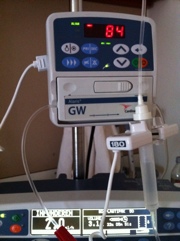

De suikerwaarden waren vandaag al hoog en steeg zojuist naar 22. Ik heb nu een nood spuitje gekregen en hoop dat het de komende nacht weer daalt.

De suikerwaarden waren vandaag al hoog en steeg zojuist naar 22. Ik heb nu een nood spuitje gekregen en hoop dat het de komende nacht weer daalt.Infuus is eraf

Het infuus is aangesloten. Gelukkig is dat ding mobiel….

Het infuus is aangesloten. Gelukkig is dat ding mobiel…. In plaats van insuline te prikken wordt het nu via mijn arm toegediend.

Dit zal ongeveer twee/drie dagen duren.

Suikerwaarden was nu 8.4. Het is nu afwachten op de dingen die komen gaan..